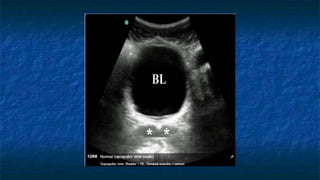

3)FAST: Pelvis exam

 Pelvis: Longitudinally and Transvers Axis.

 Probe placed

 Transeversally then Longitudinally

 Midline 2 cm superior to the symphysis pubis

 “aimed” caudally into the pelvis (prostate )

 Probe facing

 Toward patient’s head and right side.

 Best with some urine in bladder(acoustic window)

 Evaluating

 Bladder ,Uterus in female ,and Prostate in

male

 The potential spaces are Pouch of

Douglas (Cul de sac ) in female and

retrovesicle space in male

FAST: Pelvis exam

 Pelvis: Transverse Axis

 Normal Anatomy

 Evaluating Bladder

 Well cirucumscribed

 Contains fluid that

appears anechoic

FAST: Pelvis exam - Pathology

Transverse

Bladder

FF